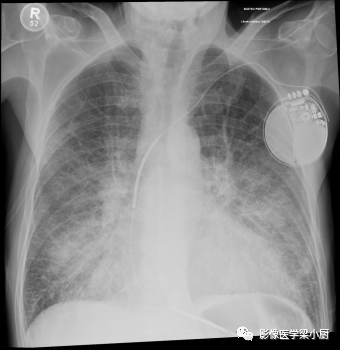

图片

间质性肺水肿X线图像,双肺小叶间隔增厚,表现为双肺下叶几乎垂直于胸膜表面的短细的水平线,称为Kelery B线。